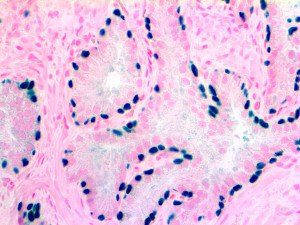

Clinical and laboratory manifestations of HLH include fever, enlarged liver and/or spleen, neurologic dysfunction, coagulopathy, liver dysfunction, cytopenias (i.e., low levels of erythrocytes, leukocytes, and/or platelets), hypertriglyceridemia, hyperferritinemia, hemophagocytosis, and eventually diminished NK cell activity as the immune system becomes progressively paralyzed. HLH can be familial (primary HLH) or secondary to another disease process (sHLH), such as rheumatic disease, in which it is referred to as macrophage activation syndrome (MAS, characterized by elevated ferritin).

This activation induces inflammatory monocytes to highly express IL-6, starting a localized and then systemic cascade effect that results in hyperproduction of IL-6, which accelerates the inflammatory process. Because IL-6 also increases vascular permeability, excessive levels cause blood vessels to become very leaky. This, along with clotting factors released from vascular endothelial cells, stimulates the coagulation cascade, resulting in microthrombosis (tiny clots), which leads to ischemia and tissue death of the kidney, intestines, heart, liver, brain and extremities.